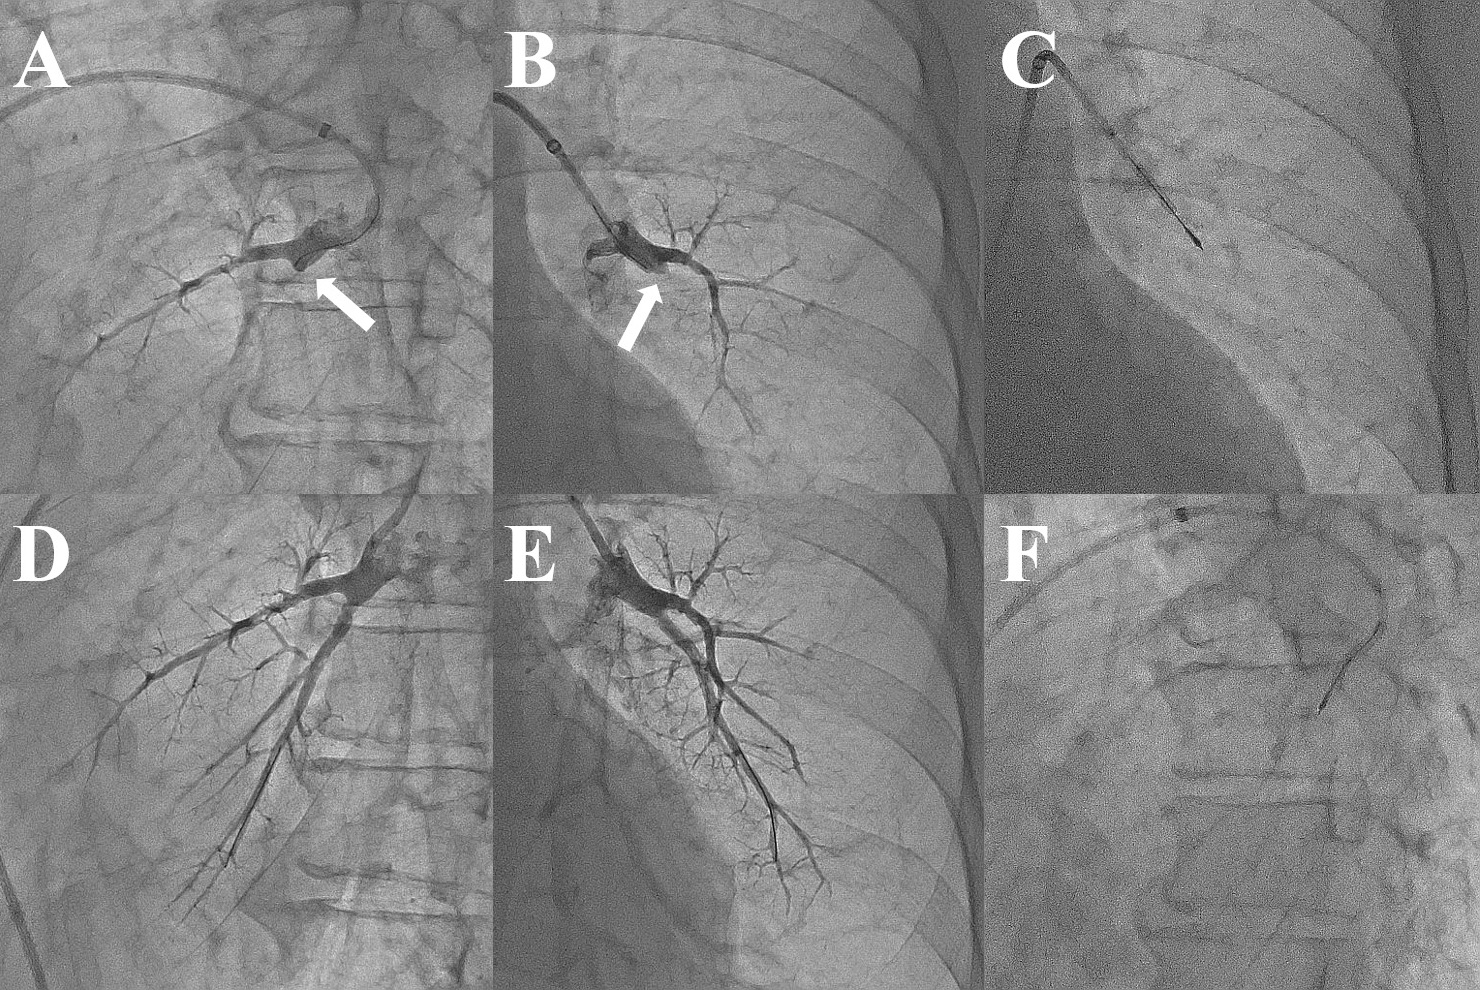

Of the 50 lesions identified as total occlusions, 27 (54%) could be passed using only the precedent IVUS technique followed by balloon dilatation to obtain Grade 2 or 3 peripheral blood flow. In 16 of the 23 unsuccessful cases, balloon dilatation was performed at the site where IVUS confirmed the vessel lumen. Of these 16 patients who underwent balloon dilatation, 13 achieved improvement in peripheral perfusion during the postprocedural phase. In the remaining 7 unsuccessful cases, balloon dilatation was not performed, at the discretion of the operator, because of the patients’ persistent cough and increased pulmonary artery pressure during the procedure. Two of these 7 patients had Grade 3 flow at the next pulmonary angiogram. As a result, 15 of the 23 unsuccessful cases showed peripheral perfusion on pulmonary angiography performed in the postprocedural phase. The balloon dilatation patients showed significantly more peripheral perfusion in the postprocedural phase than did the non-balloon dilatation patients (P = .0257) (Figure 3).

The primary outcome was initial success in opening the total occlusion lesions. Initial success was defined as a case in which the lesion was passed using the precedent IVUS technique, dilated with a balloon catheter, and pulmonary blood flow of Grade 2 or 3 was achieved. Cases that ended with blood flow of Grade 0 or 1 were considered unsuccessful.11 The secondary outcome was the presence or absence of peripheral blood flow in the postprocedural phase. Considering that there are cases in which blood flow improves in the postprocedural phase simply by breaking the cap of the thrombus layer, the presence of such blood flow was evaluated based on whether balloon dilatation was performed in cases in which the precedent IVUS technique was unsuccessful.